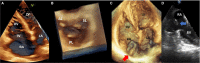

Compared with the extensive data on left-sided infective endocarditis (IE), there is much less published information on the features and management of right-sided IE. Right-sided IE accounts for 5% to 10% of all IE cases, and compared with left-sided IE, it is more often associated with intravenous drug use, intracardiac devices, and central venous catheters, all of which has become more prevalent over the past 20 years. In this manuscript on right-sided IE we provide an up-to-date overview on the epidemiology, etiology, microbiology, potential locations of infection in the right heart, diagnosis, imaging, common complications, management, and prognosis. We present updated information on the treatment of pacemaker and device infections, infected fibrin sheaths that appear to be an easily missed source of infection after central line as well as pacemaker removal. We review current data on the AngioVac percutaneous aspiration device, which can obviate the need for surgery in patients with infected pacemaker leads and fibrin sheaths. We also focused on advanced diagnostic modalities, such as positron emission tomography/computed tomography. All of these are supported by specific case examples with detailed echocardiographic imaging from our experience.